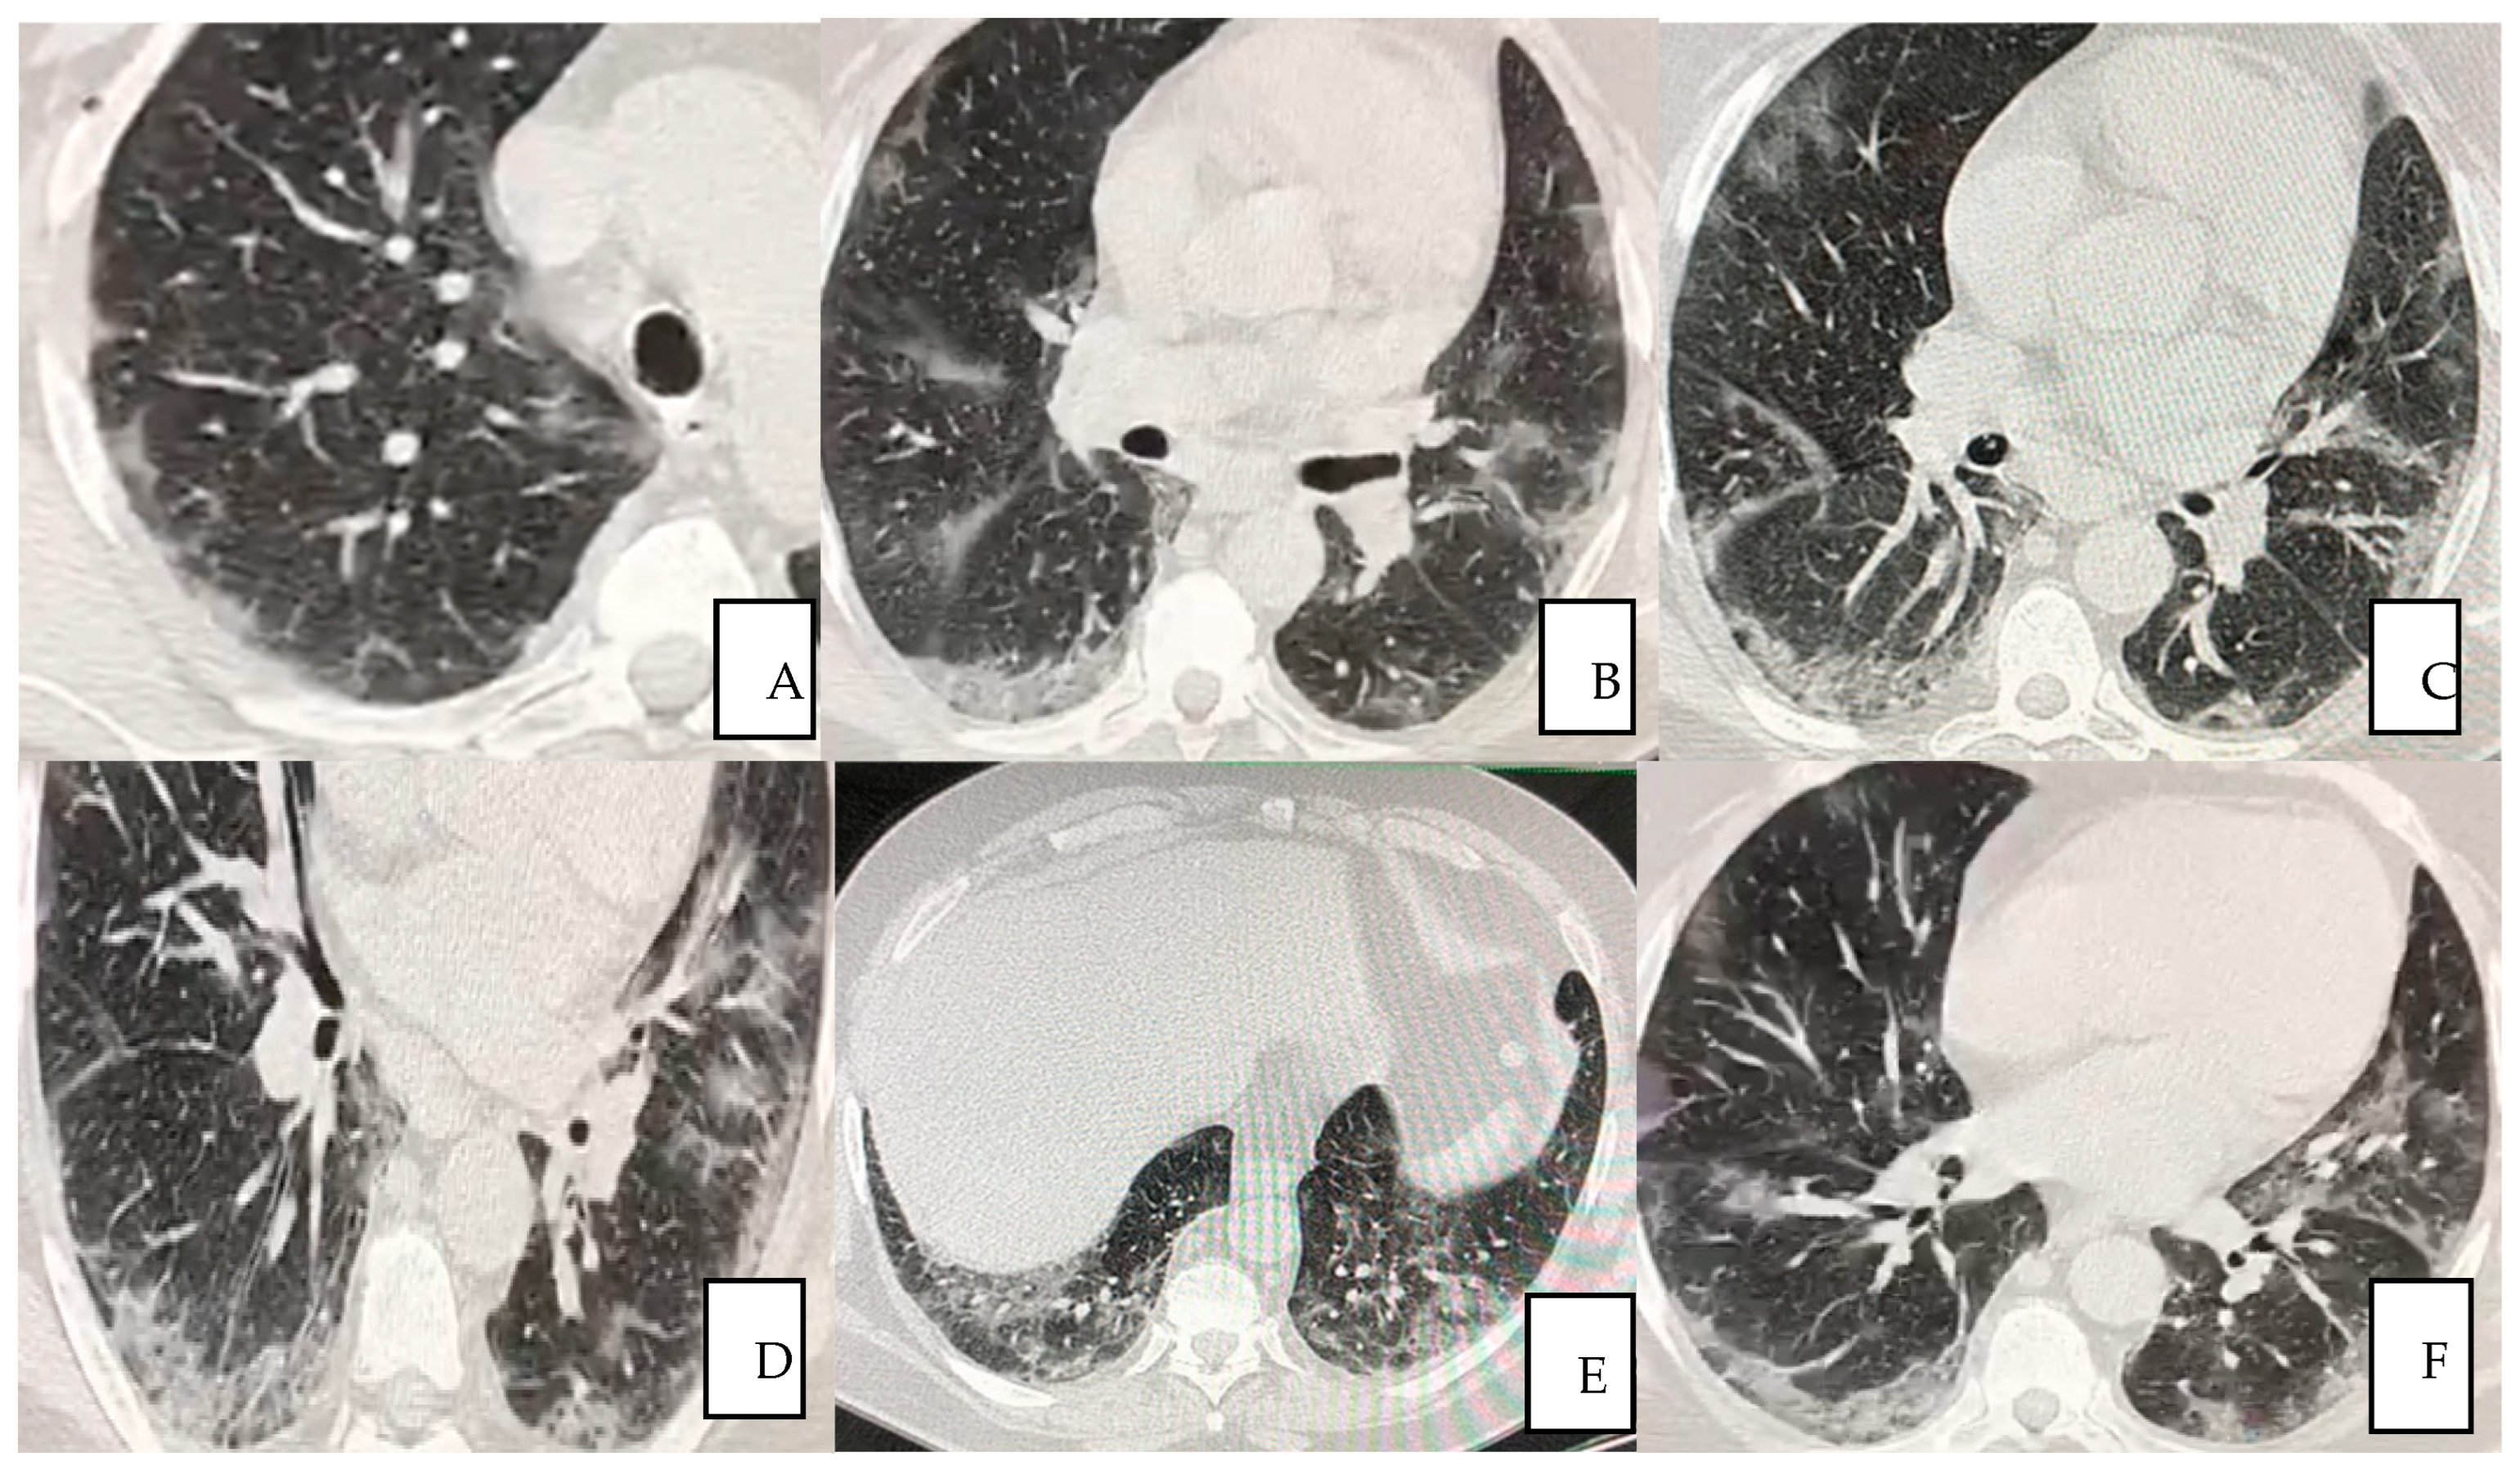

The patient was treated with autologous plasma and stem cells. He was not a smoker; he was overweight, with pre-existing medical conditions such as asthma, seasonal allergy and hypertension. He received the same protocol treatment as the other hospitalized patients as per the “SG Moscati Hospital” guidelines, composed of antiviral agent, steroid, anticoagulant and antibiotic agents. The protocol previewed 12 applications until the complete resolution of the patient. Autologous plasma administered between the day 1 and 22 days after the admission showed no collaterals, rejection or adverse events. The viral load was undetectable at day 10 in the hospital and any severe side effects were observed thoroughly the whole treatment period afterwards. At day 12, the patient was dismissed and the treatment continued on weekly bases each time measured by Complete Blood Count (CBC) analysis. Typical CT imaging of COVID-19 includes bilateral, apical, parenchymal, peripheral, and basal predominant ground-glass opacity and consolidation. The CT shows that at day 35, with a total of five plasma transfusions, the damages had been reduced by 98% (Figure 2A–C).

Figure 2.

(A–C) Pulmonary HRCT scan obtained on day 35 from symptom onset (23 December 2020) shows almost complete resolution of the initial presentation.

Serial chest CT scan during recovery from COVID-19 were performed to evaluate lung abnormalities displayed as ground-glass opacity with the development of white net pattern and increased consolidation (i.e., more extensive lung involvement), and following resolution. The severity of lung damage and the differences between patients who recovered with conventional treatment and the patient received additional autologous plasma and stem cells treatment were assessed and described by comparing CT scan images. It is worth emphasizing that patients showed interstitial lung damages even long after COVID-19 resolved (12 months), as reported in this study (Figure 4A–C).

Figure 4.

(A–C) A 56-year-old man from “SG Moscati Hospital”, Taranto, presented with fever, cough, and chest pain. Pulmonary HRCT at presentation on 3 March 2020 showed extensive peripheral predominant ground-glass opacities in both upper lobes (A); On 26 March 2020, a follow-up HRCT showed similar anomalous ground glass opacities (B) HRCT obtained on 14 May 2020 showed organizing changes with decrease in extent of the ground-glass opacities and increasing parenchymal consolidations (C).